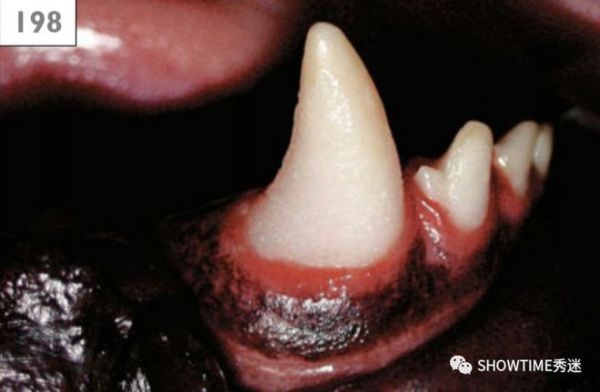

“Honey”右侧还未处理前,可以看到已经有牙结石。

如果狗狗在幼年的时候有肾脏衰竭的问题,会因为二次性的血钙缺乏,造成钙化不全的状况。钙化不全的牙釉质就失去了坚硬特质,会变软,甚至轻轻一碰就会碎裂,还会出现染色。没有成熟的牙釉质虽然看起来大小形状是正常的,但是颜色会显得偏白又不透明,非常容易破损,用探针轻易的就可以在上面画出一道划痕。

可以看到它们长出来的成齿表面缺乏牙釉质,变得黄黄的,而且显得很粗糙。有的狗狗会出现像是下面图中的环状缺损,也有的狗狗会出现整颗牙齿都没有牙釉质的情况。

当缺损是因为局部的受伤或是感染,牙釉质的缺损会以局部区域或是点状的方式出现。

牙釉质环状缺损。

牙釉质完全缺损。